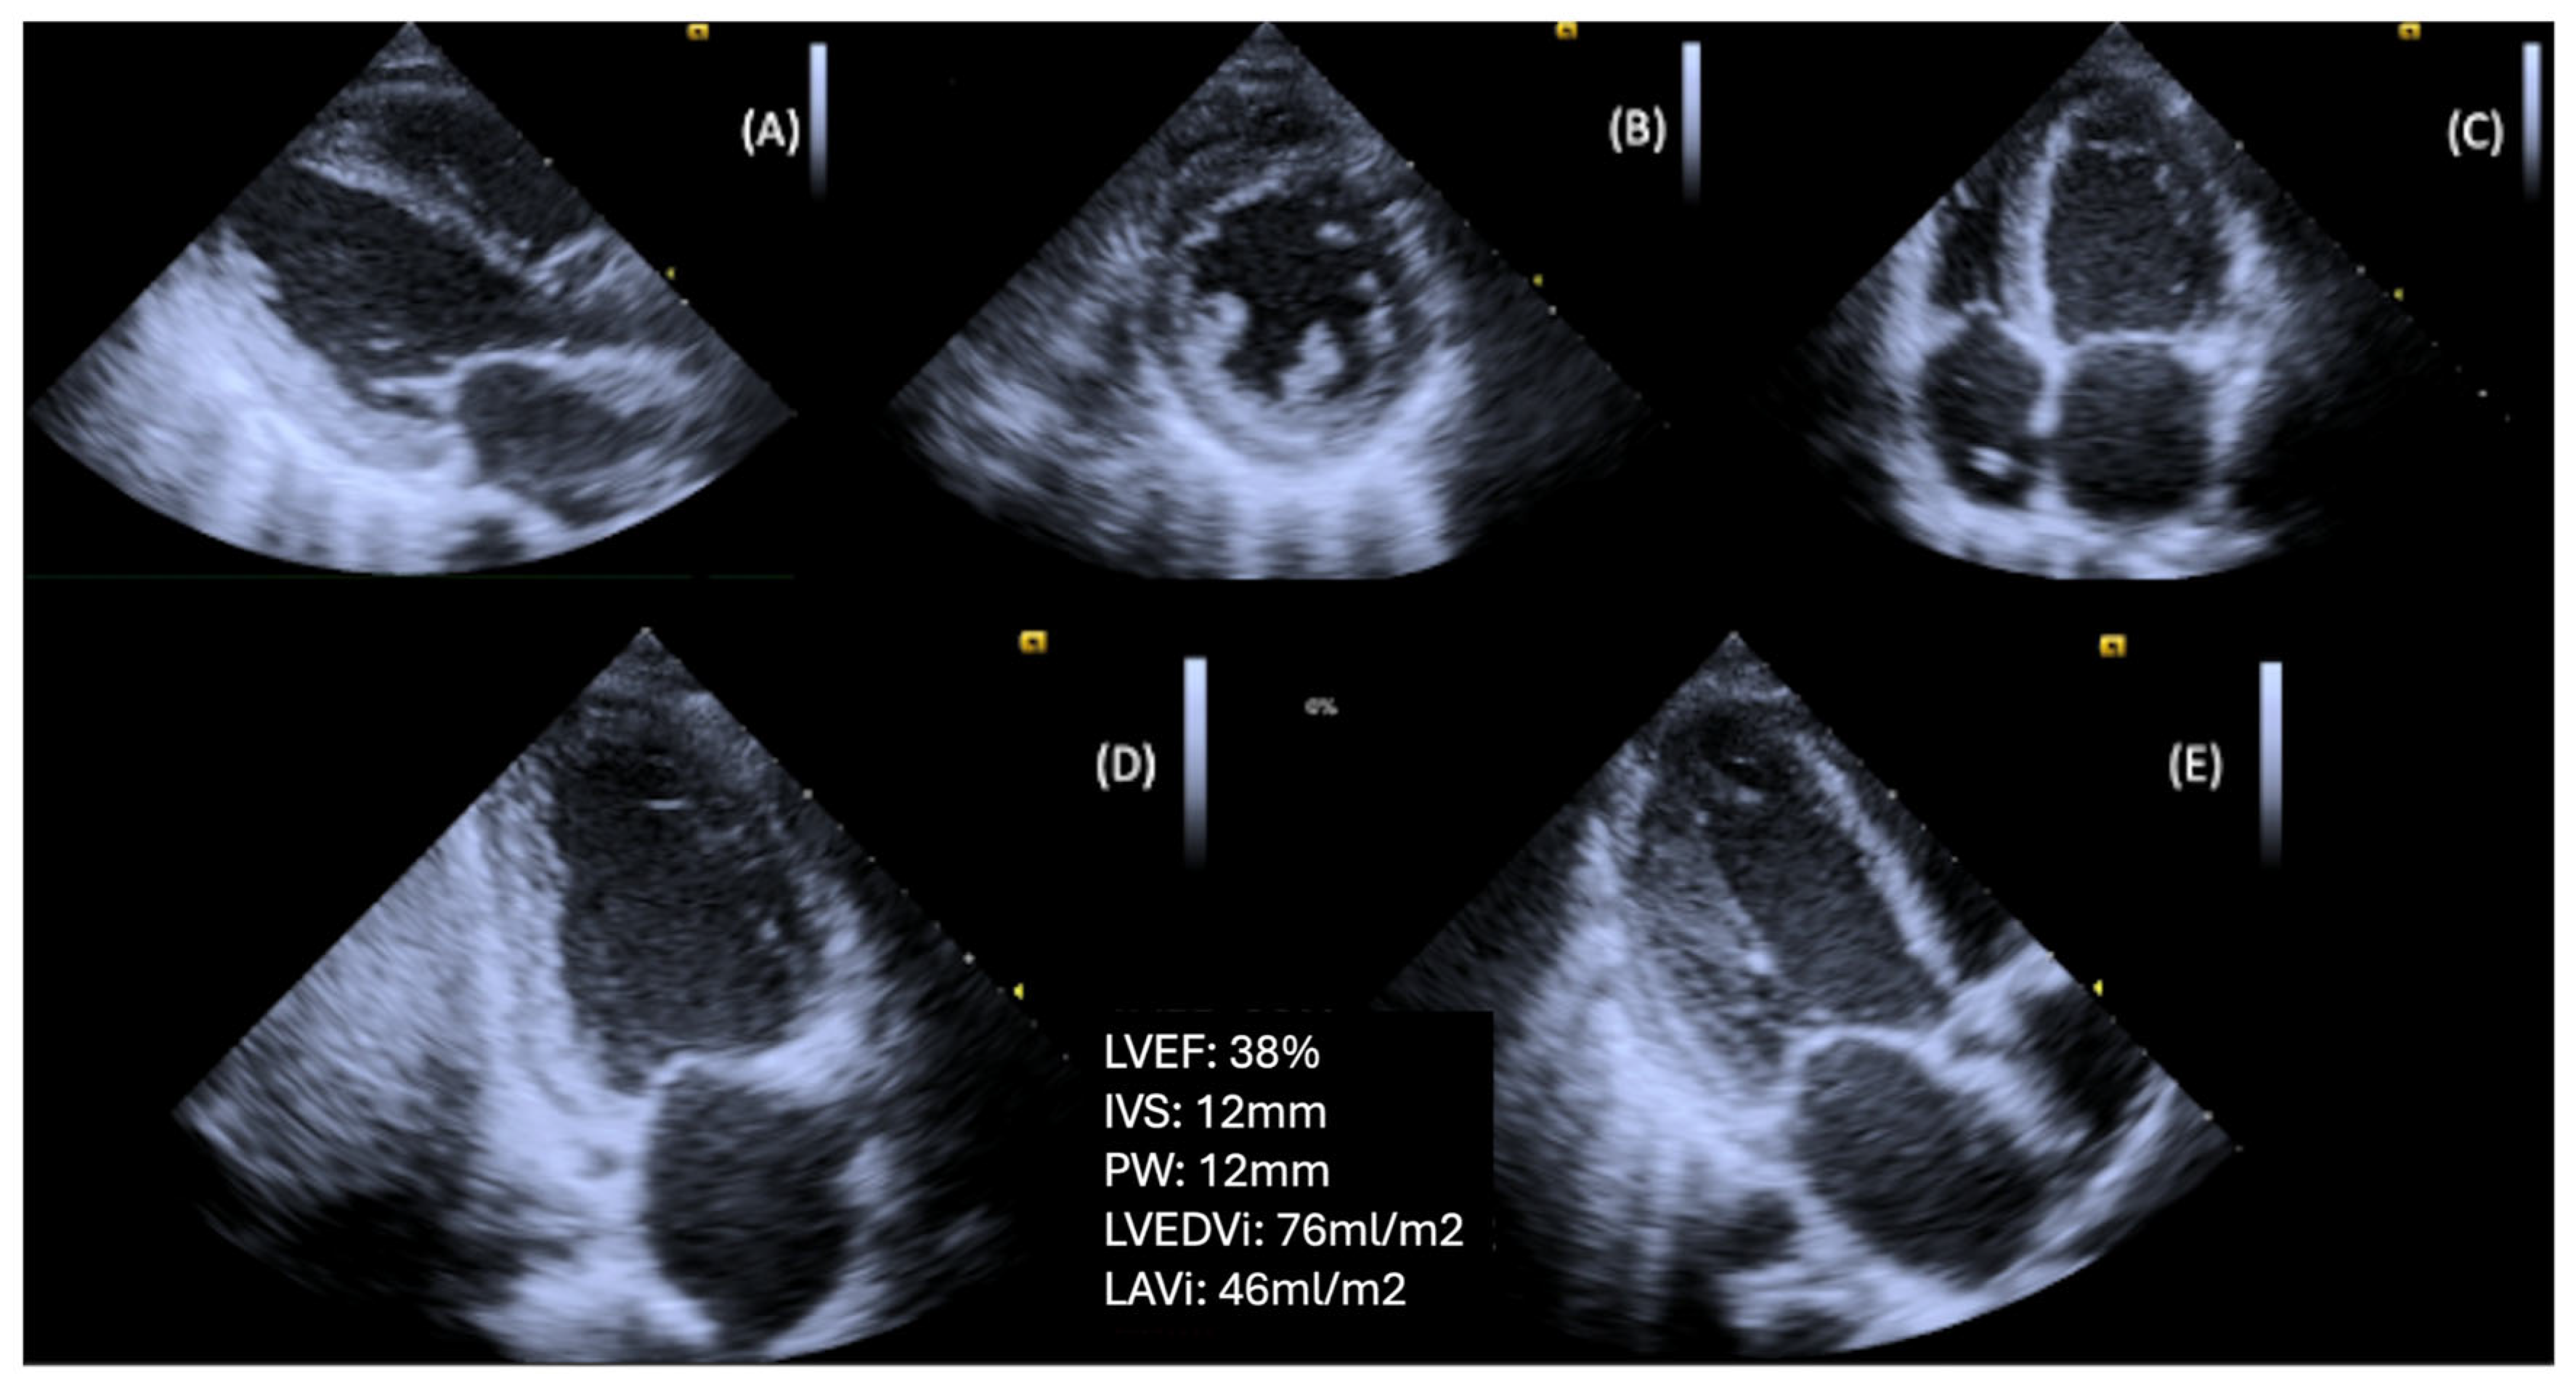

3.3. LV Systolic Dysfunction

| LV systolic function | LVEF (Simpson) | LVEF may be normal at early stage; volumetric method better than 2D dimension assessment | Reversely associated with increased HF hospitalization, CV morbidity and mortality |